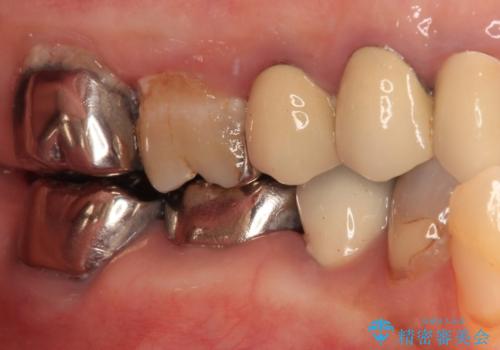

銀歯を外したところ、非常に大きなむし歯が認められましたが、神経組織には及んでおらず、速やかにオールセラミッククラウンによる補綴治療を行いました。